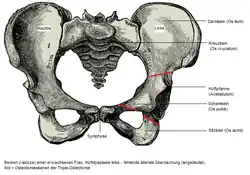

Zur Planung einer Hüftendoprothese wird die ap-Aufnahme als Beckenübersichtsaufnahme durchgeführt. Dies bedeutet, dass beide Hüftgelenke dargestellt werden. Diese Aufnahme kann im Stehen oder im Liegen durchgeführt werden.

Das Röntgenbild kann auch Auskunft über präarthrotische Deformitäten, beispielsweise bei einer Hüftdysplasie (vgl. Abb.) als Ursache der Coxarthrose geben.[18] Hier ist der Hüftkopf nicht ausreichend überdacht und steht deswegen dezentriert nach oben / seitlich heraus. Dadurch resultiert eine Verkürzung der Beinlänge. Im Laufe der Zeit kommt es zu einer massiven „Entrundung“ des Hüftkopfes, der Gelenkspalt ist fast ganz aufgehoben, das Hüftgelenk wird steif.

- Chiari-Osteotomie: Durchtrennung des Darmbeins oberhalb der Pfanne und Schaffung eines künstlichen Pfannendachs durch Verschiebung des Azetabulums

- Salter-Osteotomie: Durchtrennung des Darmbeins und Herunterschwenken des Pfannendachs

- Triple-Osteotomie: Durchtrennung von Darmbein, Sitzbein und Schambein und anschließend die Drehung der Hüftpfanne